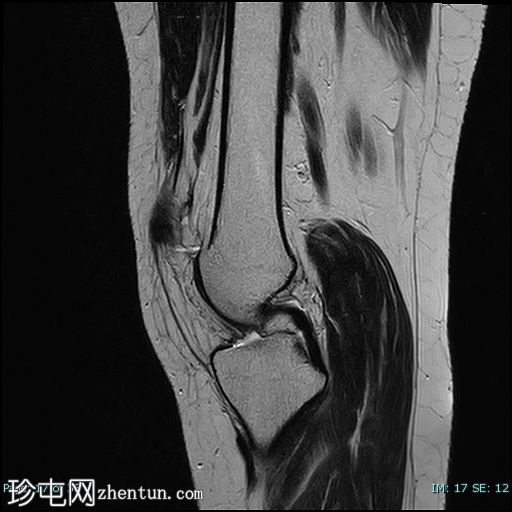

矢状位

PD序列

4.jpg

髌骨高位(Insall-Salvati比值=1.7),伴外侧半脱位。内侧髌骨支持带及内侧髌股韧带变薄、缺损、松弛。

外侧髌骨关节面软骨内T2/STIR/PD信号强度增高,伴下方骨髓囊性改变和水肿。

外侧Hoffa脂肪垫水肿。

外侧髌骨关节面软骨软化。

股四头肌腱和髌腱正常。

本病例展示了霍夫脂肪垫撞击综合征的典型特征,伴有髌骨高位和髌骨外侧半脱位。

患者症状最常见的潜在病因被认为是髌骨轨迹异常。